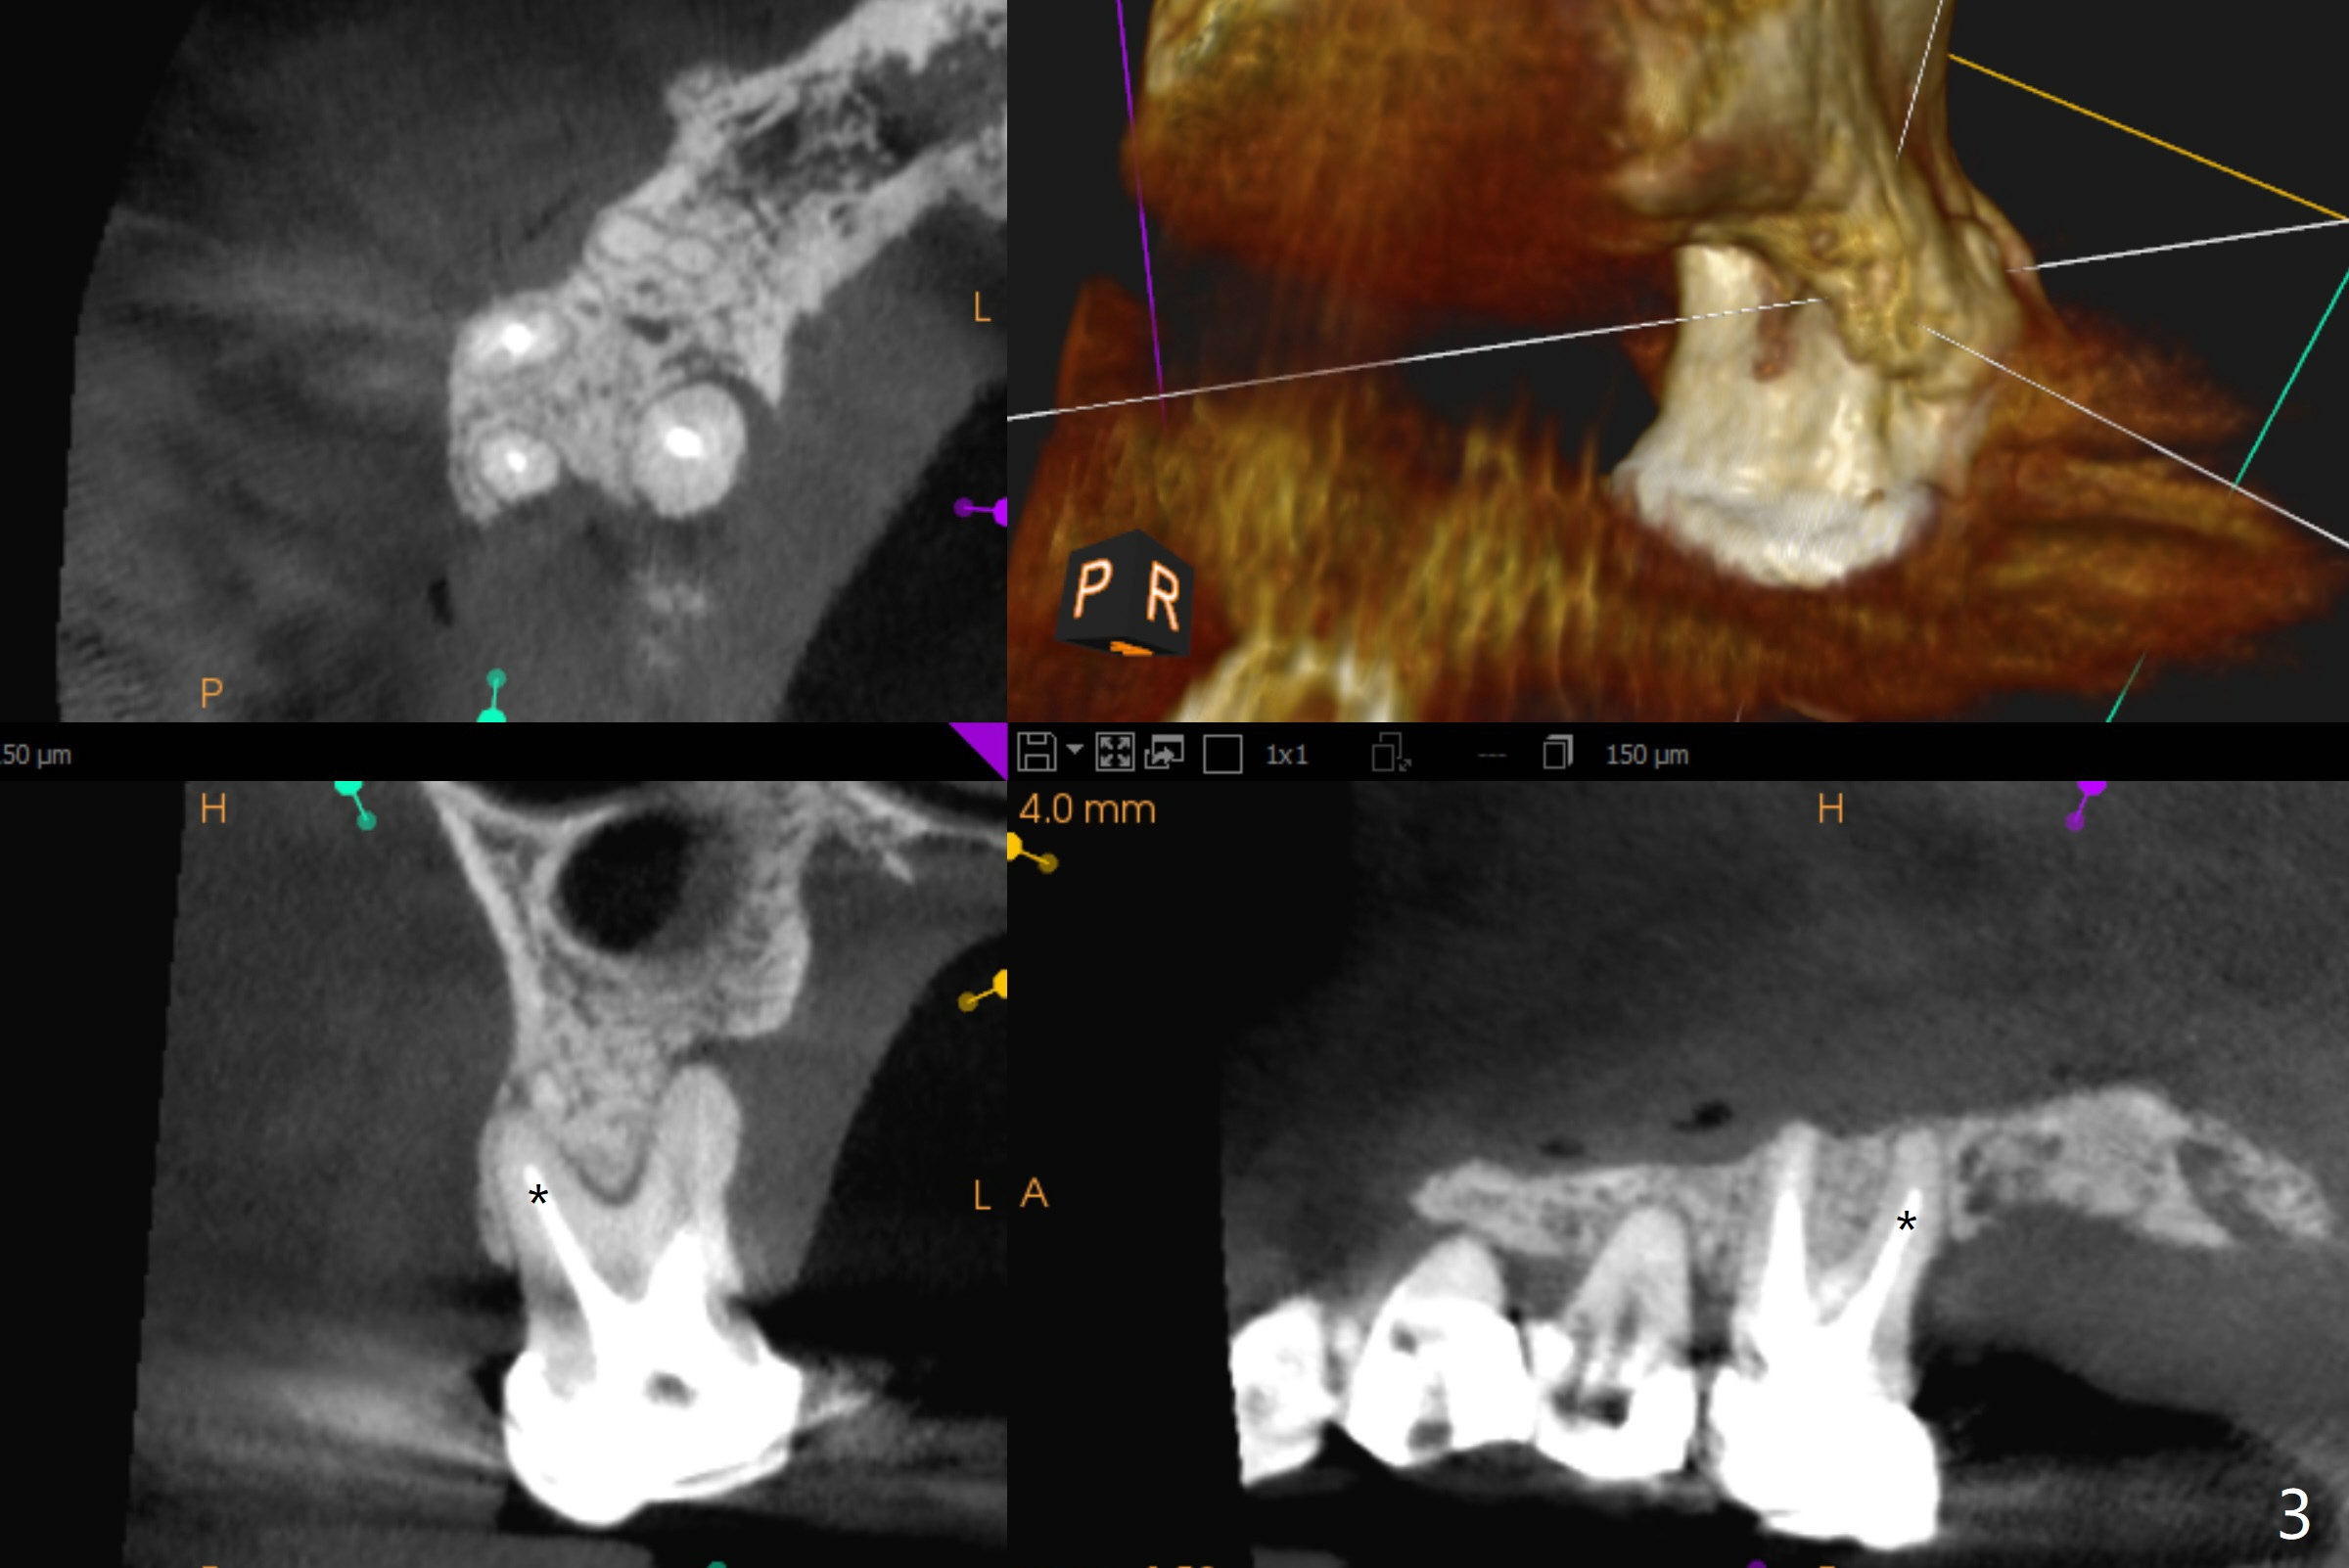

A 52-year-old woman has had chronic abscess associated with the tooth #3. The palatal root is exposed (Fig.1 P), suggesting root fracture. The apex of the mesiobuccal root seems to stick out of the buccal plate (Fig.2 *). The root canal filling is incomplete in the distobuccal root (Fig.3 *). The tooth appears to have guarded prognosis. Extraction and immediate implant is apparently a better option (Fig.4,5). It would be safer to start osteotomy in the middle of the remaining septum (Fig.6, as compared to Fig.5). After sinus lift with PRF membrane (Fig.7 yellow curved line) and implant placement (green), another piece of PRF membrane will be placed against the palatal wall of the socket, followed by bone graft (red circles) and a 25-degree angled abutment (pink).